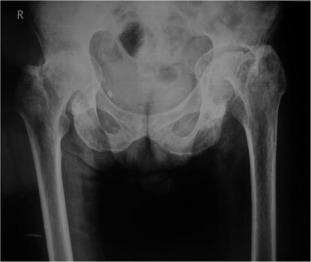

Pre-operative x-ray of a patient with protrusio acetabuli.

Fig. 3.

There were 61 patients (50 male, 11 female) with 105 affected hips (72% bilateral, 28% unilateral). The average patient age at surgery was 41.3 ± 10.2 years old. The age of patients at THA was as follows: <30 years for 14 patients (23 hips), 31–50 years for 41 patients (73 hips) and >50 years for 6 patients (9 hips) (Graph 1 ). The younger age at diagnosis (<30 years old) of AS was correlated with younger age at THA (p < 0.05). Bone ankylosis was detected in 37 (35%) and acetabular protrusion was noticed in 18 (17%) hips in pre-operative radiographs (Fig. 1 , Fig. 2 , Fig. 3  ;  Fig. 4 ) (Table 1 ). The mean pre-operative flexion contracture was 20.3°±21.8°. In patients without ankylosis, the mean total hip range of motion (ROM) was 67.8°±25.7°.